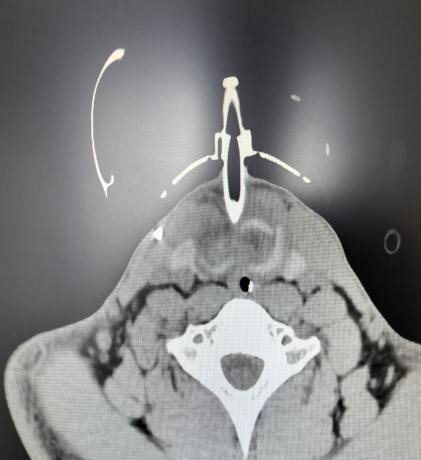

患者入院时虽神志尚清,但已出现声音嘶哑、颈部疼痛、胸闷气喘等危险信号,血氧饱和度持续下降。我院急诊团队评估后立即启动最高级别预警,迅速完成生命体征监护和检查的同时,敏锐地察觉到患者颈部正在快速肿胀,这是皮下气肿的典型表现,预示着气道可能存在严重破损。我院耳鼻喉科专家通过喉镜探查,做出了关键性判断:高度怀疑喉软骨骨折、气管断裂。后续CT检查结果印证了这一判断,患者双侧颌面部、颈部、胸部乃至纵隔内出现了大量积气。更危急的是,断裂处漏出的气体已形成双侧张力性气胸,双肺被压缩均近50%,心脏和大血管严重受压,情况十分危急!

随后,患者被转入EICU(急诊重症监护室)进行高级生命支持。面对创伤性湿肺、纵隔皮下大量气肿、潜在的感染风险以及脑积水等复杂情况,在全身麻醉下,我院耳鼻喉科、麻醉科、呼吸内科等科室组成的专家团队为患者进行了急诊手术。术中发现患者环状软骨下方多个气管环前方碎裂,右侧环状软骨缺损严重。手术团队精准操作迎难而上,为患者精细清创,彻底清理了颈部淤血及游离的碎骨片,为重建创造基础。随后,在纤维内镜辅助下进行气道探查,明确损伤范围,确保无遗漏。同时,术中巧妙地将右侧咽壁内环状软骨膜与左侧带状肌缝合,顺利完成喉部功能重建,并缝合了颈前碎裂的气管。手术最后顺利拔除临时细套管,更换为更安全的7.5号气切套管,保障了术后气道的通畅与安全。